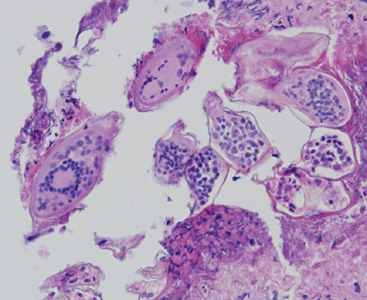

A 58-year-old female who had emigrated from Africa was seen by her health care provider for complications with squamous cell carcinoma of the cervix. CT scans of the pelvis revealed a small mass in the bladder. Biopsy specimens of the bladder and subsequent bladder washings were sent to Pathology for histological work-up. Microscopic examination of the specimens by the attending pathologist revealed structures suggestive of a parasite. Digital images were sent to the DPDx Team for diagnostic assistance. Figures A–D show what was observed in the biopsy specimens, stained with hematoxylin and eosin (H&E). Figures E and F show what was observed in the bladder washings, stained with Papanicolaou stain. The object in Figure E measured 150 micrometers in length. What is your diagnosis? Based on what criteria?

Figure A

Figure B

Figure C

Figure D